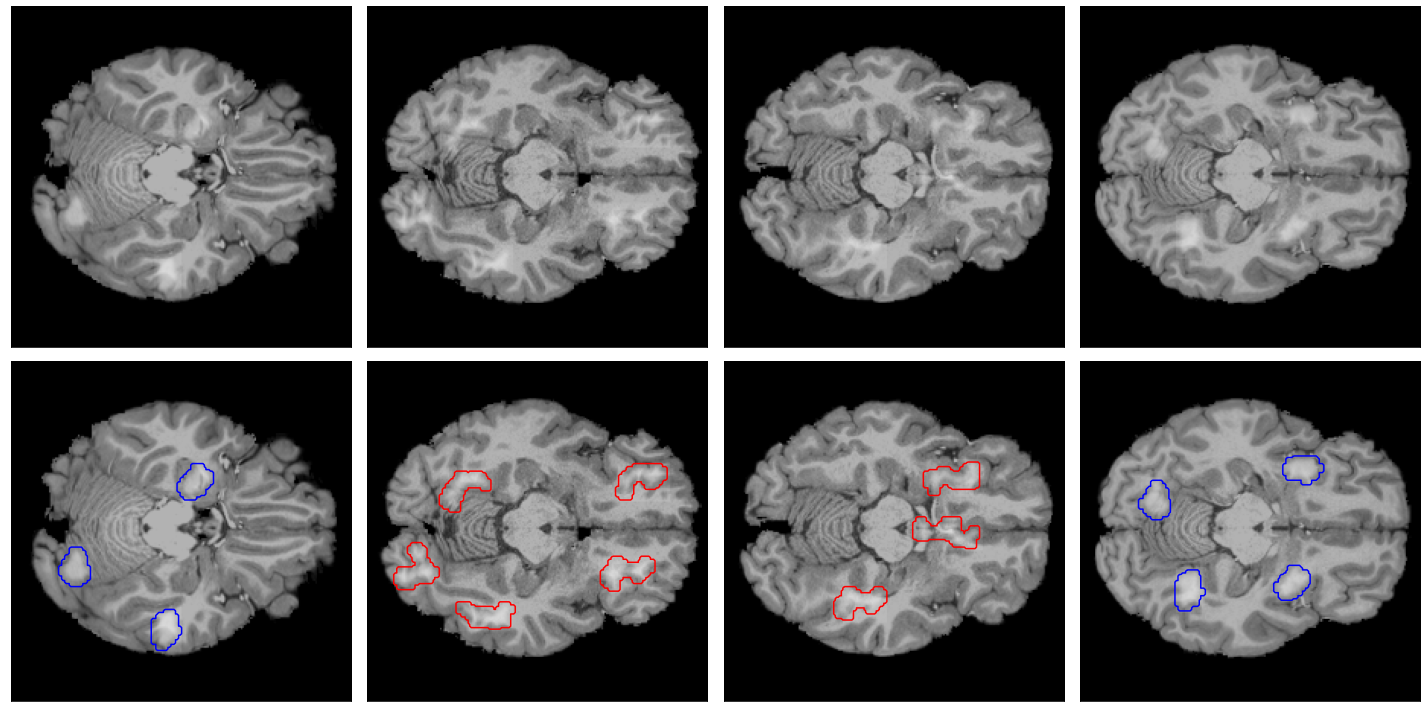

Refer to caption

Figure 1: Example of images of the dataset created. The top row consists of axial MRI slices from the Human Connectome Project (HCP, hcp) healthy brain dataset, with artificial lesions added. The bottom row consists of the top row images, but with the position of these lesions contoured in blue, forming the ground-truth for an explanation.

From the images obtained after the application of the morphological operations, the connected components (contiguous groups of non-zero intensity pixels fully surrounded by zero intensity pixels) are identified, which serve as lesion candidates. Further, lesions are selected based on the compactness of their shape. Here, it is sufficient to consider the isoperimetric inequality on a plane Ap2/4πA\leq p^{2}/4\pi, where AA\in\mathbb{R} is the area of a particular lesion shape and pp\in\mathbb{R} its perimeter. The compactness is obtained by comparing the shape of the lesion candidate to a circle with the same perimeter. The larger the compactness, the rounder the shape. Here, regular lesions are required to have a compactness above 0.80.8 and irregular lesions have a compactness below 0.40.4. After selecting the lesions, they are padded with a 2-pixel margin, and a Gaussian filter with a radius of 0.750.75 pixels is applied to smooth the lesion boundaries. Examples of obtained lesions are displayed in Figure 1.